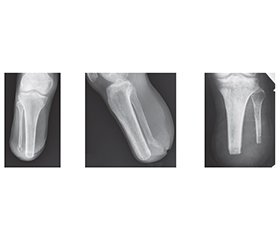

Background. Stress fractures of amputation stumps of the lower extremities are an understudied complication of prosthesis use that develops against the background of impaired bone remodeling and repeated mechanical stress. Aim: to investigate the clinical, radiological, and morphological features of stress fractures of lower limb amputation stumps and to determine their relationship with the timing and nature of prosthetic rehabilitation. Materials and methods. Twenty-three patients aged 21–49 years with stress fractures of lower limb amputation stumps were examined at various times after prosthetic fitting. A clinical assessment of pain syndrome and gait function was performed, as well as an X-ray examination with analysis of the condition of the cortical layer and trabecular architectonics, morphological examination of bone tissue based on materials from revision surgical interventions. Additionally, an analysis of systemic and local risk factors for stress fractures was performed. Statistical processing of the results was made using parametric methods, with a statistical significance level of p < 0.05. Results. It was found that early stress fractures (≤ 4 months after prosthetic fitting) form against the background of incomplete structural and functional formation of the stump and active reparative osteogenesis; in 72 % of cases, they occur within the first 2.5 months and are accompanied by moderate disturbances in cortical and trabecular architectonics. Fractures in this group were localized mainly in areas of maximum mechanical stress and anatomical vascular vulnerability. Late stress fractures (> 4 months after prosthetic fitting) were characterized by severe osteoporosis, hyperostosis, cystic remodeling of the medullary canal, and gross disruption of the trabecular structure, reflecting chronic pathological remodeling of bone tissue. Bilateral amputation was associated with accelerated formation of stress fractures regardless of the timing of prosthetic replacement. Conclusions. Stress fractures of lower limb amputation stumps are the result of an imbalance between bone remodeling processes and repeated mechanical stress. The timing and quality of prosthesis use, gait biomechanics, and a combination of systemic and local factors determine the nature and rate of damage development, which justifies the need for an individualized approach to prosthetic rehabilitation and a phased load dosage.